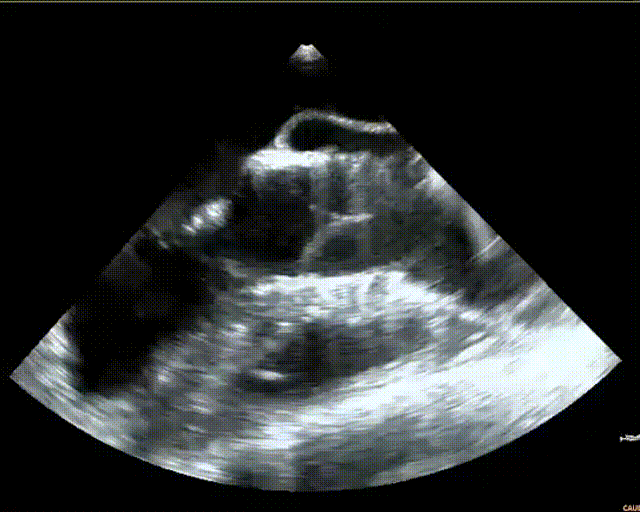

术前超声评估

术后即刻超声评估

停起搏,缓慢释放瓣膜脱钩。观察几分钟,TaurusElite®AV29mm瓣膜锚定良好,未下滑。术后造影结果显示瓣膜形态、位置良好,无瓣周漏。手术即刻超声测量,主动脉瓣工作良好,无反流。